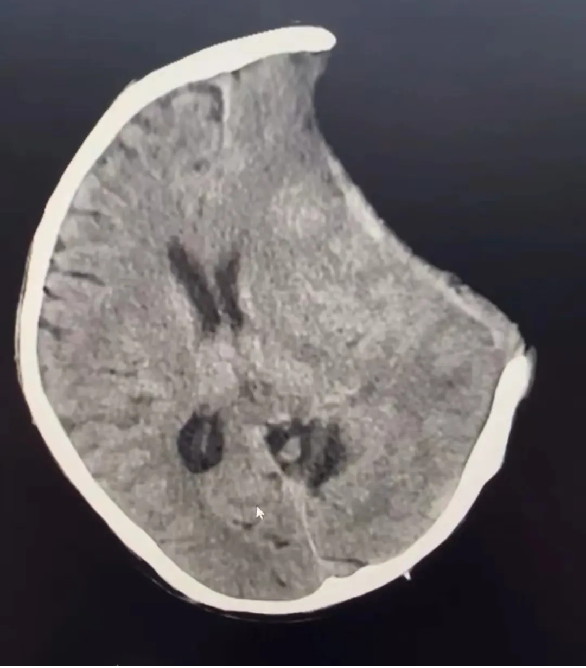

術前:

術後: